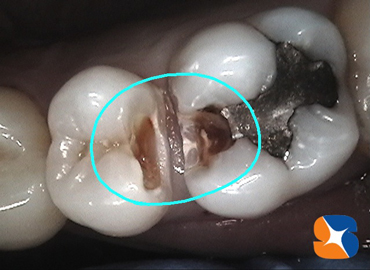

百聞は一見に如かず。最近、歯科用ビデオをPanasonic製に機種変更。画像がかなり美しく鮮明になり、患者様からも「とても分かりやすい!」と好評。

当院では、虫歯をビデオで撮影して患者様に報告しています。虫歯の存在を口で伝えるだけでなく、実際に見て確認して頂くことを目的にしています。

〈症例〉暗くて最も見えにくい上の奥歯もビデオで確認していただいています。